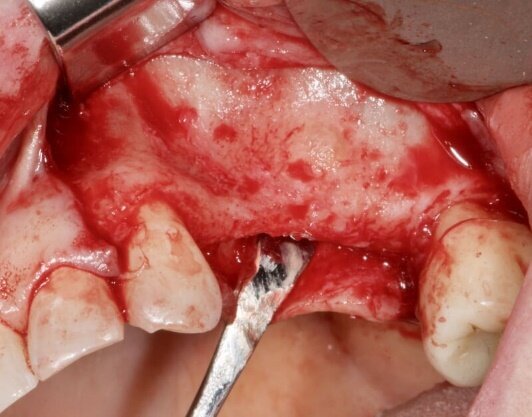

In fase preoperatoria è stato prescritto aerosol (2 volte al giorno per 7 giorni) con beclometasone dipropionato (Clenil 0,8 mg/2 ml) e soluzione ipertonica (Libenar 22g/l) a partire da 7 giorni prima dell’intervento e antibiotico (Amoxicillina 1 g - ogni 12 ore a partire dal giorno precedente l’intervento per 6 giorni). È stato eseguito il rialzo di seno mascellare del secondo quadrante per via laterale abbinato a una contestuale tecnica di GBR/Guided Bone Regeneration (Figg. 4-6). Come sostituto osseo è stato utilizzato lo xenoinnesto bovino Re-Bone® (Ubgen, Padova, Italy) da 1 g con granuli cortico-spongiosi 0,25-1 mm (Figg. 7, 8, 11). Questa metodica è stata abbinata a Shelter ® membrana in pericardio bovino (Ubgen, Padova, Italy) fissata poi con appositi pins ritentivi (Figg. 12, 14, 15). Terminata la tecnica di GBR, sono stati suturati i lembi (Vicryl, 4/0, Johnson & Johnson Int.) (Fig. 16).

Il rialzo del seno mascellare è una procedura, quindi, spesso necessaria per riabilitare pazienti mediante impianti endossei nella regione posteriore del mascellare superiore. Per la tecnica di rialzo del seno mascellare sono stati utilizzati strumenti piezoelettrici che riducono i disagi delle tradizionali tecniche osteotomiche, semplificano e codificano le sequenze operative e permettono di ottenere incrementi di svariati millimetri del pavimento sinusale. La procedura GBR, Guided Bone Regeneration, prevede l’utilizzo di membrane che fungono da barriera per evitare l’invasione delle cellule epiteliali e connettive dei tessuti molli circostanti, fornendo così cellule osteogeniche, che riportano una velocità di migrazione più lenta e quindi migliori condizioni per la rigenerazione ossea. La membrana in pericardio bovino, fissata con pins ritentivi, grazie alla peculiare struttura del collagene a trama larga di matrice tridimensionale viene riassorbita dall’organismo senza alcun processo infiammatorio nell’arco di 4-5 settimane.